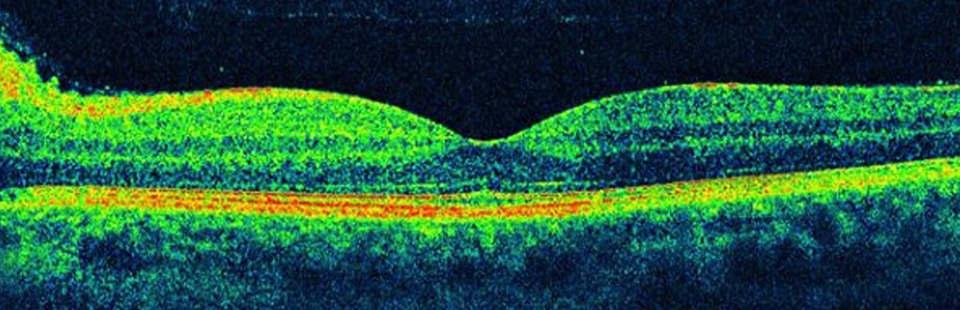

Диагностика зрения: Когерентная томография сетчатки

Раздел: Фотоальбом решений